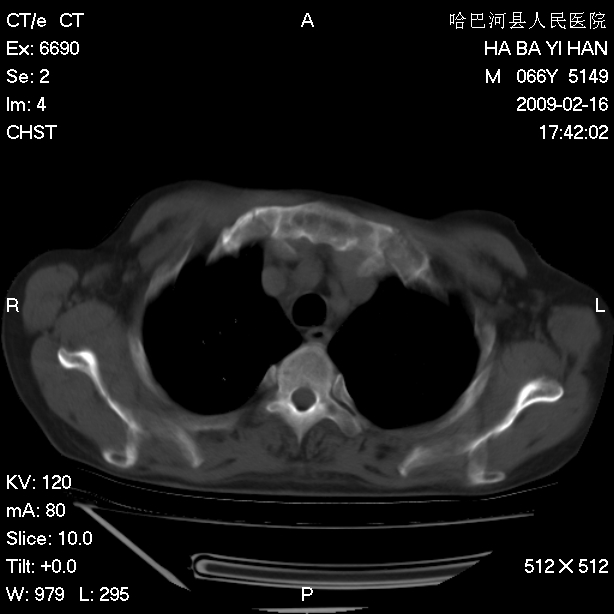

以下是引用huangxun4321在2009-2-16 20:18:00的发言:[br]部分病灶可见硬化边,部分可见骨质破坏消失,部分病灶内可见骨脊,说明病灶内既有良性病变,又有恶性病变,考虑骨巨细胞瘤恶变,未除骨纤恶变,畸形性骨炎少见,亦要考虑.

以下是引用731208在2009-2-16 20:31:00的发言:[br]考虑恶性胸膜间皮瘤并肋骨,脊柱转移。

以下是引用yijiansheng在2009-2-16 20:16:00的发言:[br]考虑恶性胸膜间皮瘤并肋骨,脊柱转移。

以下是引用形影不离在2009-2-16 19:55:00的发言:[br]考虑多发性转移瘤。